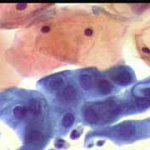

Papanicolaou: Πλακώδη επιθηλιακά κύτταρα κυρίως της επιφανειακήςστιβάδας, περίπου κατά50% και πλέον οξεόφιλα (16η ημέρα κύκλου!) . Ωστόσσο και αρκετά της διαμέσου και της παραβασικής, εν μέρει με διογκωμένους, ανισομεγέθειςαρραιοχρωματικούςδιαυγείςπυρήνεςKοιλοκυττάρωση.Η εικόνα συνηγορεί για δυσπλασία σοβαρού βαθμού.

Λόγω και του κολποσκοπικούευρήματος, μικροβιοψία που κατεδειξε ιστολογικώς CIN III